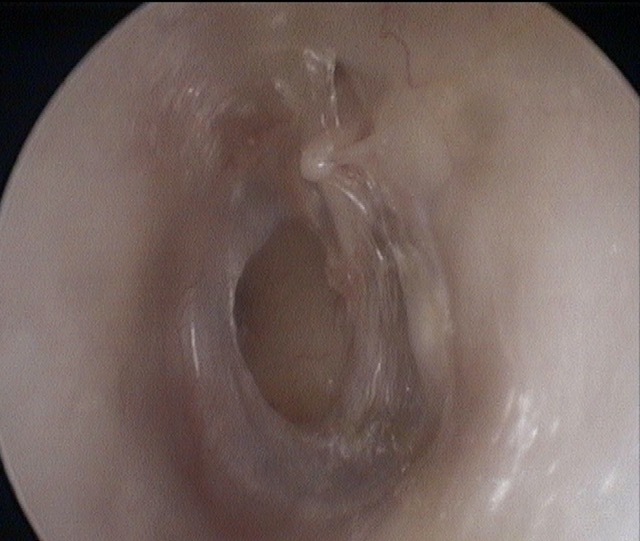

Perforation